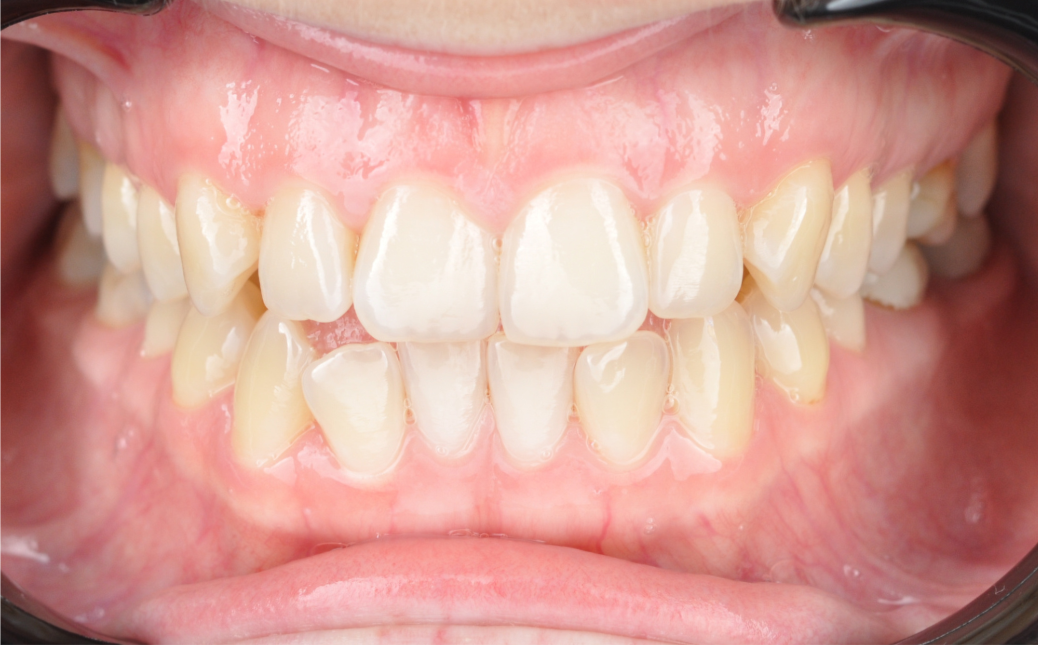

Результаты комплексного лечения

Комплексный подход команды «Архитектор Улыбок» дал закономерный результат, который был спрогнозирован еще

до старта лечения.

Здоровая улыбка

Ушел дискомфорт в суставе, исчезли боли в процессе жевания. Нижняя челюсть заняла стабильное, физиологичное положение.

Восстановилась функция

Качество жевания кардинально повысилось, процесс приема пищи снова стал комфортным.

Эстетика

Исправлен прямой прикус, восстановлена форма резцов, а улыбка стала не только красивой, но и здоровой с точки зрения биомеханики.